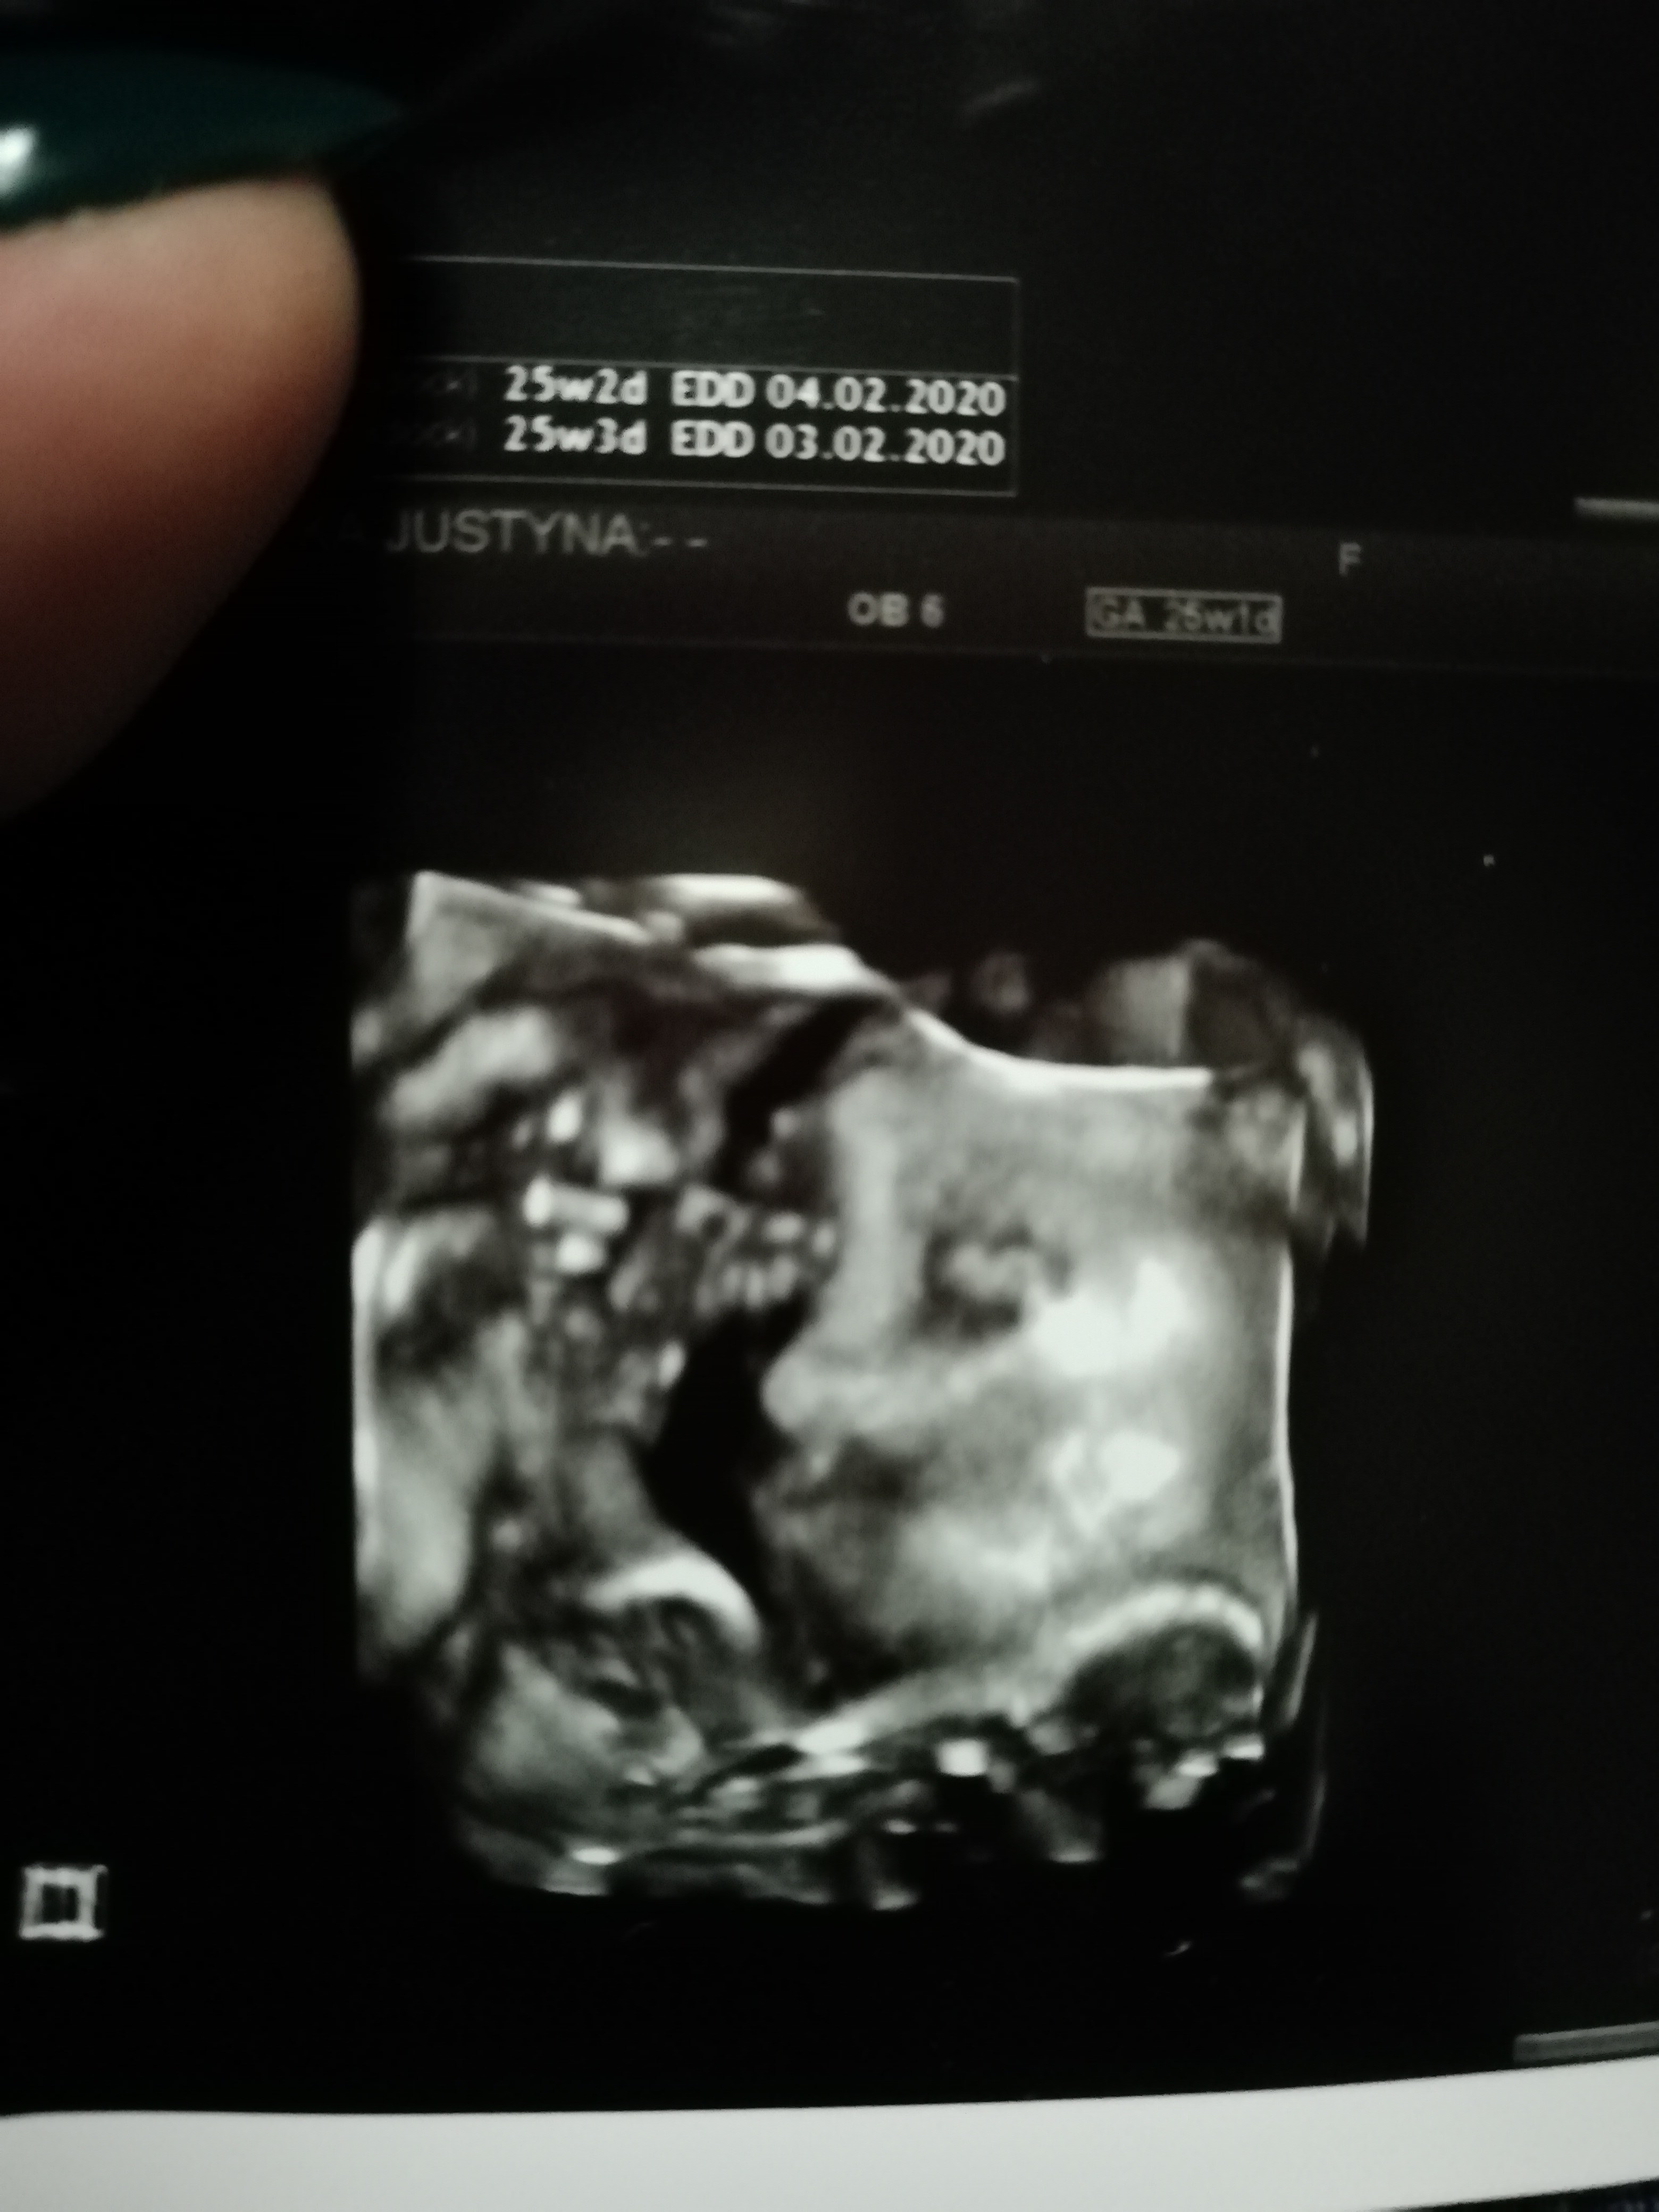

Tu podobno widac siusiaka, cos na ksztalt siusiaka, raczej siusiaka